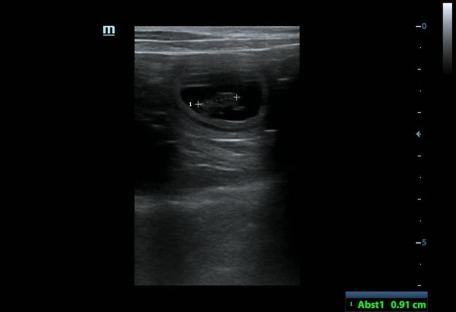

Ultraschall 09.04.2021

Wir haben 9 Fruchtblasen gezählt!